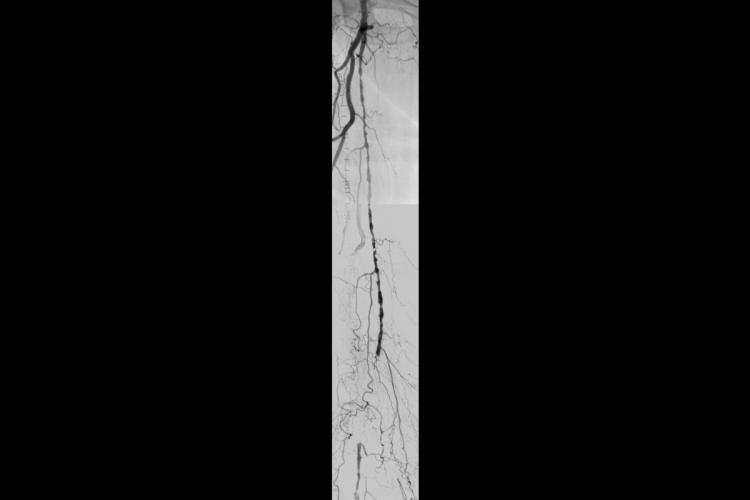

Endovascular treatment of chronic superficial femoral artery (SFA) occlusion for limb salvage

A case study using the GORE® VIABAHN® Endoprosthesis with Heparin Bioactive Surface*,†

Challenge

- 83-year-old female with ischemic gangrene of right great toe (Rutherford 6)

- Pulse volume recordings demonstrated femoropopliteal occlusive disease

Procedure

- Contralateral approach to right SFA (March 05, 2013)

- Lesion crossed using straight TERUMO GLIDEWIRE® Guidewire, followed by placement of SPECTRANETICS® QUICK‑CROSS Support Catheter

- Percutaneous transluminal angioplasty (PTA) with 5 mm angioplasty balloon